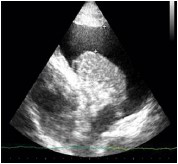

Assinale a opção que apresenta a imagem de ultrassonografia pulmonar compatível com a descrição do quadro acima.